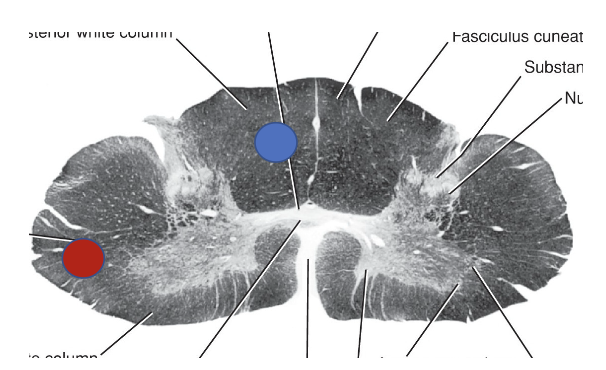

The axons travelling in the blue dot area are carrying what type of information for which side of the body?

Blue dot = Posterior white column: carrying conscious proprioception, 2-point tactile and vibratory sense from the RIGHT side of the body

Red dot = 2nd order neuron carrying pain and temp sensation from the LEFT side of the body